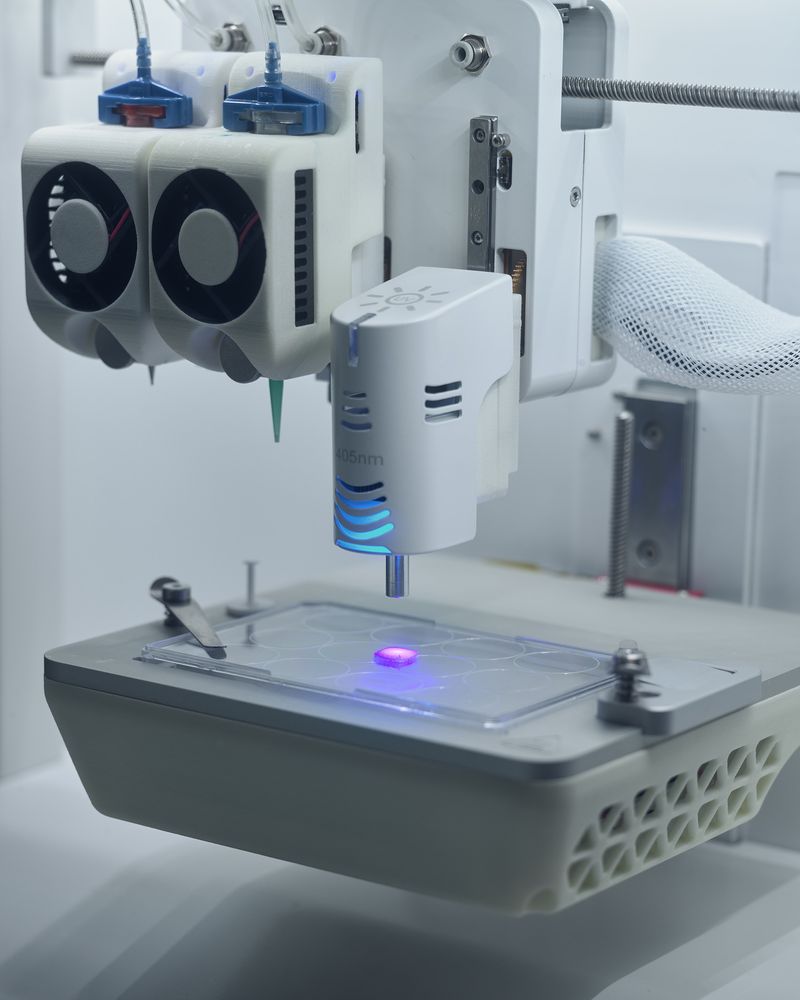

My work asks questions and challenges contemporary social and cultural attitudes towards the perception of death, the quality of life, reflections on the essence of humanity on philosophical and technological grounds. The story of our corporeality aims to begin a discourse about what has been tabooed or is socially marginalized:

medical bioengineering, technology in medical service, change in the perception of a dead body and the aspect of loss. Such a discourse could reveal the needs and solutions for the development of bioengineering in Poland. The increasingly appearing idea of transhumanism in this aspect considers dysfunctional elements of the human condition, such as disability, suffering, disease and ageing, to be undesirable, often still remaining only an idea but also a goal.